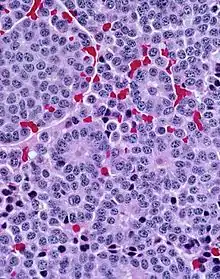

Very high magnification With prominent rosettes

With prominent rosettes